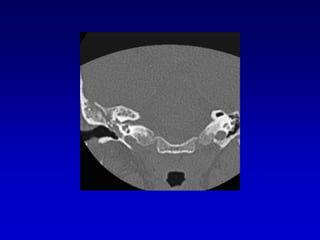

Bulbo yugular dehiscente